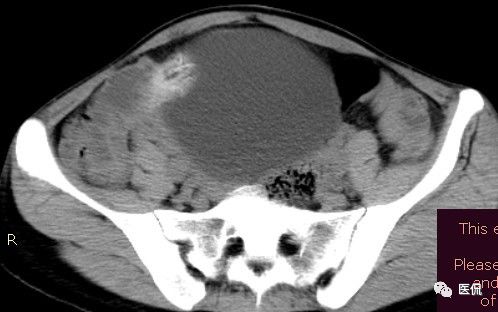

腹腔内残留的纱布在人体内引起渗出或液化坏死并纤维包裹形成异物性脓肿(纱布瘤)。纱布瘤的影像特点:圆形或卵圆形肿块,较大,有完整包膜,薄壁,较少的情况下为厚壁,边界较完整,增强后薄膜可以持续强化。不同时期的纱布瘤可以有不同表现:早期(10个月或半年内)多表现为蜂窝状;2~5年内一般表现为囊性飘带状;10~20年之后则为实性软组织密度,包膜钙化呈钙化网状结构。手术过程中残留在人体内的医用纱布所形成的肿瘤样病变。

手术所见:腹腔内无腹水,肿块位于右上腹,约15x10x8cm大小 ,周围网膜包裹粘连,向胆囊三角处延续,呈囊性,与周围结构无明显浸润,仔细分离粘连,逐步游离暴露肿块,见肿块与右肾及结肠、十二指肠无明显关系,初步确定为肿大的胆囊,继续向肝门部游离,见肿块与胃窦粘连,因分离困难,决定切开肿块。穿刺肿块有黄色脓液抽出,考虑胆囊脓肿,切开囊壁,吸出大量黄色混浊脓液约1200ml,探查囊腔,见粘膜层为胆囊粘膜,腔内有一异物残留,经证实为医用盐水纱布,取出纱布约15x15cm大小,封存。继续游离胆囊至完整切除,检查囊壁无明显占位病变。

病理诊断:胆囊异物残留,胆囊化脓性炎、胆囊脓肿。